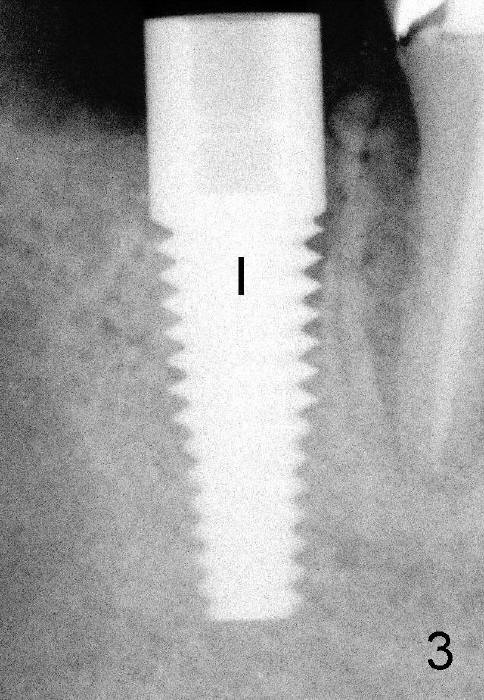

Three and a half months postop, the bone grows into the threads of the implant (Fig.5 <, as compared to the same area of Fig.3,4 (immediately postop).